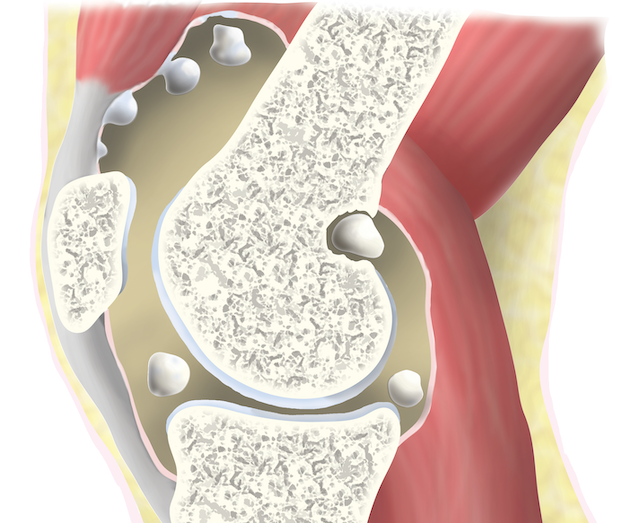

Синовиальная оболочка состоит из особых клеток, определяющих ее функциональную активность. Но при хондроматозе происходит их замещение хрящевой тканью с образованием плотным узелков. При проведении диагностических исследований они визуализируются в виде единичных или множественных бугорков. Большая часть узелков «встроена» во внутреннюю поверхность суставной сумки, а некоторые возвышаются над ней на ножке. Такие уплотнения со временем отделяются и начинают свободно передвигаться во внутрисуставном пространстве. Они состоят из гиалинового хряща, включающего очаги обызвествления.

Хондромные тельца округлые, прочные, отличаются друг от друга размерами. Обычно их диаметр не превышает несколько миллиметров, но встречаются крупные 4-5-сантиметровые экземпляры. В коленном суставе может одновременно находиться до нескольких сотен свободно перемещающихся внутрисуставных тел. Метаплазия синовиальной оболочки становится причиной ее деструкции:

Наблюдается лимфоидная и плазматическая инфильтрация, обычно спровоцированная развитием реактивного синовита. Такие образования доброкачественные, хорошо устраняются хирургическим путем. Но в медицинской литературе описаны случаи перерождения клеток, озлокачествления хондроматоза.